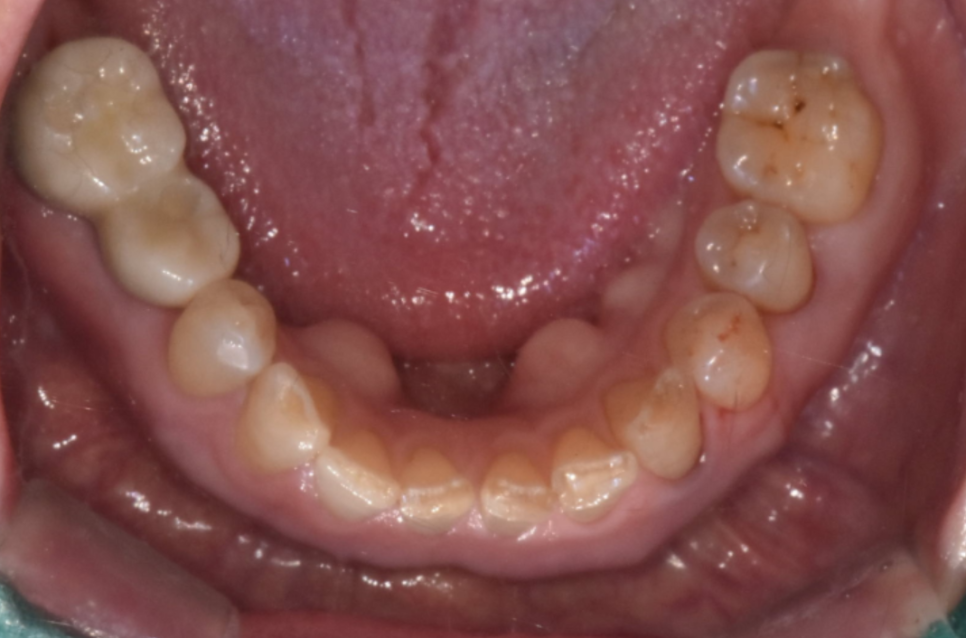

먼저 위 아래 맞물림을 확인합니다.

250724 x-ray를 찍어 보철이 매끄럽게 들어갔나 확인도 해보고요

임플란트의 보철의 높이나 형태를 미세하게 다듬으면

대부분 증상이 개선됩니다.

양쪽 균형이 중요한데

보철을 끼우는 날에는 안쓰던 치아를 사용하다보니

높이가 간혹 높아도 괜찮다고 하시는 분들이 많거든요~